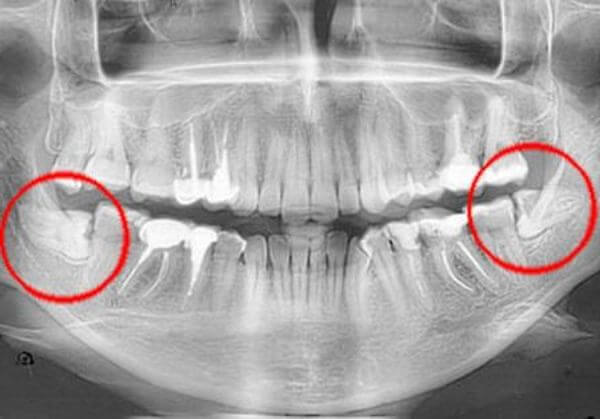

Зубы мудрости на рентгеновском снимке

Третьи моляры относятся к многокорневым зубам и обычно имеют от трех до пяти корней. При раннем прорезывании некоторые корни могут остаться недоразвитыми – увидеть это можно только на рентгеновском снимке, который рекомендуется всем после прорезывания восьмерок, чтобы изучить их строение и оценить возможные риски в будущем.

В зубном ряду третьи моляры занимают самое крайнее положение и замыкают зубную дугу. Отсутствие при визуальном осмотре еще не говорит, что у человека их нет: иногда восьмерки находятся в толще десны. Такая патология называется ретенцией, как она выглядит смотрите на фотографии.

На следующем этапе нужно сделать ортопантомограмму. Панорамный рентгеновский снимок дает максимально четкую картинку, на которой видно, как располагаются восьмерки по отношению к остальным зубам. Снимок позволяет более точно определиться со схемой лечения.

где находится и как выглядит зуб мудрости на ОПТГ

В процессе роста зуб мудрости может зацепиться за соседний моляр и развернуться под десной. В таком случае есть вероятность, что наружу он уже не покажетсяЕсли притесненному зубу повезет, он может все-так прорезаться, но частично. Или криво — тогда его называют дистопированным.Красными стрелками на рентгене обозначены дистопированные «восьмерки» у пациента